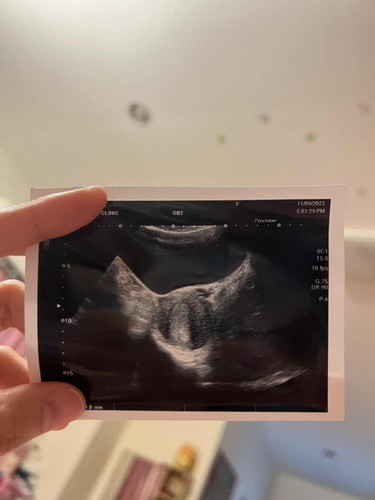

ประจำเดือนเราล่าสุด 4-10 สิงหาคม เราปล่อยมีน้องครั้งเดียว วันที่ 19 สิงหาคม ตอนนี้ตรวจแล้วพบว่าตั้งครรภ์ คุณหมอแจ้งว่าอายุครรภ์ 5 สัปดาห์ ลองซาวน์แล้วไม่เห็นอะไร แต่เราก่เอ๊ะใจว่าจะ 5 สัปดาห์ได้ยังไงอ่า 😅 หมอนัดอีกครั้งวันที่ 18 ควรไป หรือรออีกอาทิตย์ค่อยไปดีคะ #ขอบคุณสำหรับคำตอบค่ะ #ท้องแรกคะ #คุณแม่ๆช่วยแนะนำหน่อยค่ะ

การนับอายุครรภ์จะนับจากวันที่มีประจำเดือนครั้งล่าสุดค่ะ ไม่ใช่นับจากวันที่ปฏิสนธินะ ส่วนอายุครรภ์ 5 วีค ยังไม่เห็นอะไรหรอกค่ะ อย่างมากเห็นได้แค่ถุงไข่แดง จะเห็นชัดๆต้อง 8 วีคขึ้นไปค่ะ

เราไปหาหมอตอน5สัปดาเหมือนกันคะ ตอนนั้นยังไม่เห็นตัวน้อง เห็นแค่ถุงน้ำคร่ำ รออีกสัก3-4อาทิตย์คะ ไปหาหมอรอบต่อไปเห็นแน่ๆ

รอซาวน์เจอตัวน้องแล้ววัดขนาดก่อนนะคะ จะได้รู้อายุครรภ์จริงๆ ตอนนี้หมอนับตามปจด. ซึ่งวันไข่ตกอาจคลาดเคลื่อนได้ค่ะ